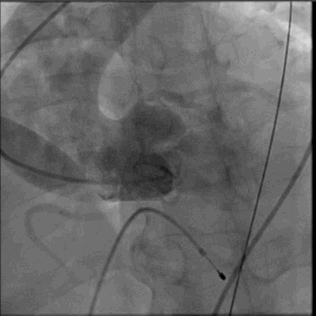

输送系统到位

圈套器snare 协助输送系统安全准确达到预计区域,猪尾主动脉根部造影确认系统和窦底的相对位置,调整重置锚定区